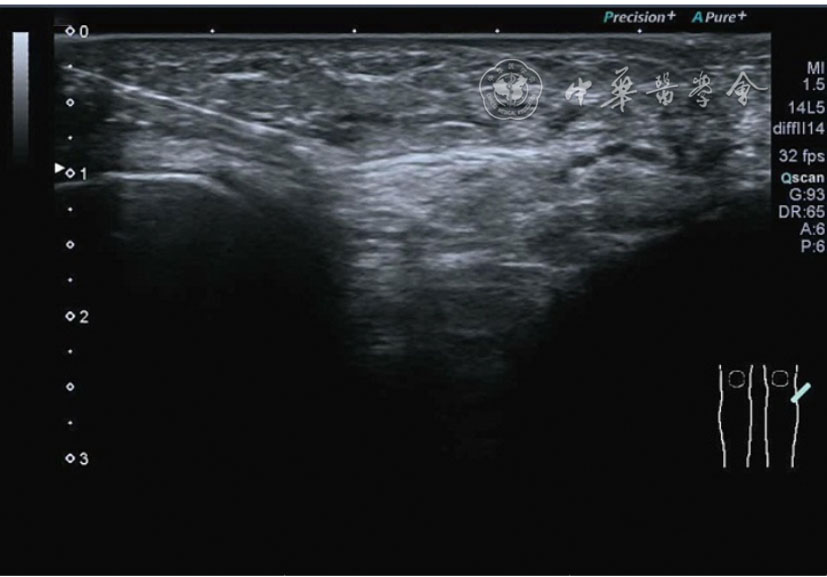

3.超声半定量评估。(1)骨赘超声半定量评估:患者仰卧位,膝关节伸直,探头纵切面置于膝关节内侧与外侧,自前向后移动探头以进行全面扫查。测量骨赘的厚度,并进行半定量分析。0级:无骨赘;1级:小骨赘,厚度<2 mm;2级:中等骨赘,厚度2.1~4.0 mm;3级:大骨赘,厚度>4.0 mm。(2)关节软骨超声半定量评估:患者仰卧位,膝关节完全屈曲。探头置于骨上方,检查股骨内侧髁、外侧髁和股骨滑车处关节软骨三个部位,分别进行横切面和纵切面检查,从近侧向远侧做全面扫查。检查时声束要垂直于股骨表面。关节软骨可按病变严重程度分为四级。0级:关节软骨呈均匀的无回声带,其浅侧和深侧边界清晰。1级:关节软骨浅侧边界不清和(或)内部回声增高。2级:①2A级,关节软骨局部变薄,缺损厚度<50%;②2B级,关节软骨局部变薄,缺损厚度>50%,但<100%。3级:关节软骨局部完全消失,伴或不伴有软骨下骨病变。(3)半月板突出分度:半月板外周缘与胫骨平台边缘之间的距离≥3 mm的突出视为病理变化,诊断为半月板周缘滑脱。按照突出程度分为三度:Ⅰ度,半月板外周缘与胫骨平台边缘之间的距离3~5 mm;Ⅱ度,半月板外周缘与胫骨平台边缘之间的距离>5~8 mm;Ⅲ度,半月板外周缘与胫骨平台边缘之间的距离8 mm以上。